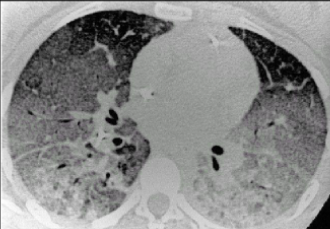

張新民介紹,在初步臨床研究的基礎上,治療結果表明,干細胞治療新冠肺炎患者安全有效,可以快速緩解或停止加重重癥和危重癥患者的呼吸困難。臨床表現、呼吸功能、影像學等方面均有改善,一般 8 - 10 天達到治愈水平。此外,干細胞在阻斷肺纖維化過程和促進肺損傷修復方面的作用表明,干細胞對預防肺纖維化和改善新冠肺炎患者的長期預后具有獨特的優(yōu)勢。

間質性肺病是指許多急性和慢性肺實質病變引起肺泡壁和肺泡腔不同程度的炎癥和纖維滲出,導致彌漫性肺間質纖維化發(fā)展的一組疾病。其病理變化可嚴重影響肺泡上皮細胞和毛細血管內皮細胞的功能和氣體交換,導致疾病晚期呼吸衰竭。

急性呼吸窘迫綜合征( ARDS )是一種嚴重的免疫性和炎癥性疾病,其特征是肺部廣泛炎癥。它是一種臨床綜合征,其特征是由多種病因引起的呼吸窘迫、低氧血癥、彌漫性肺浸潤和呼吸衰竭的快速進展。目前,缺乏有效的藥物治療。